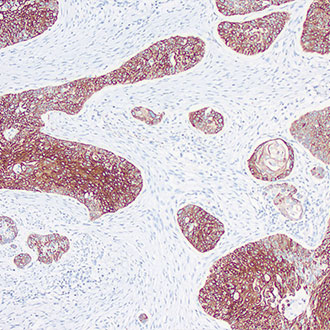

AMACR

AMACR -